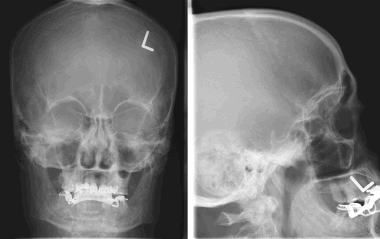

Рентгенография при менингиоме

В большинстве случаев обзорная рентгенография черепа не обладает диагностической ценностью, поскольку не позволяет получить никаких данных, которые могли бы указывать на наличие менингиомы. Иногда могут отмечаться кальцифицированные участки или зоны реактивного гиперостоза. В редких случаях могут быть видны участки остеолиза.

8. На рентгеновском снимке во фронтальной плоскости хорошо заметно кальцифицированное образование в области лобной пазухи. На снимке в латеральной проекции образование визуализируется кверху от решетчатой пластинки. Несмотря на то, что по результатам исследования можно заподозрить, обнаруженные признаки неспецифичны, и поэтому обнаруженное внутричерепное образование требует дообследования при помощи КТ.

Большинство рентгеновских снимков не отображают признаков наличия заболевания. Менингиомы типа en plaque характеризуются диффузным гиперостозом, чаще в области крыла клиновидной кости и птериона. Такие результаты исследования с большой долей вероятности свидетельствуют о наличии

болезни.

Кальцинаты внутри опухоли являются значительно более редким рентгенографическим проявлением менингиомы; это зачастую приводит к ложно-отрицательным результатам. Большинству пациентов не проводится рентгенографическое исследование, поскольку диагноз был подтвержден при помощи КТ или МРТ.